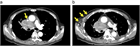

病態

1. 上大動脈症候群とは、上大静脈の閉塞や狭窄によって生じる上半身からの静脈血の還流障害により、静脈圧の上昇を来し、頭部、顔面、上肢、頚部および上半身のうっ血・浮腫を来す症候群である。

1. その原因として肺癌など胸部悪性疾患が多く、腫瘍に関連する救急疾患(Oncologic emergency)の1つに位置づけられている。